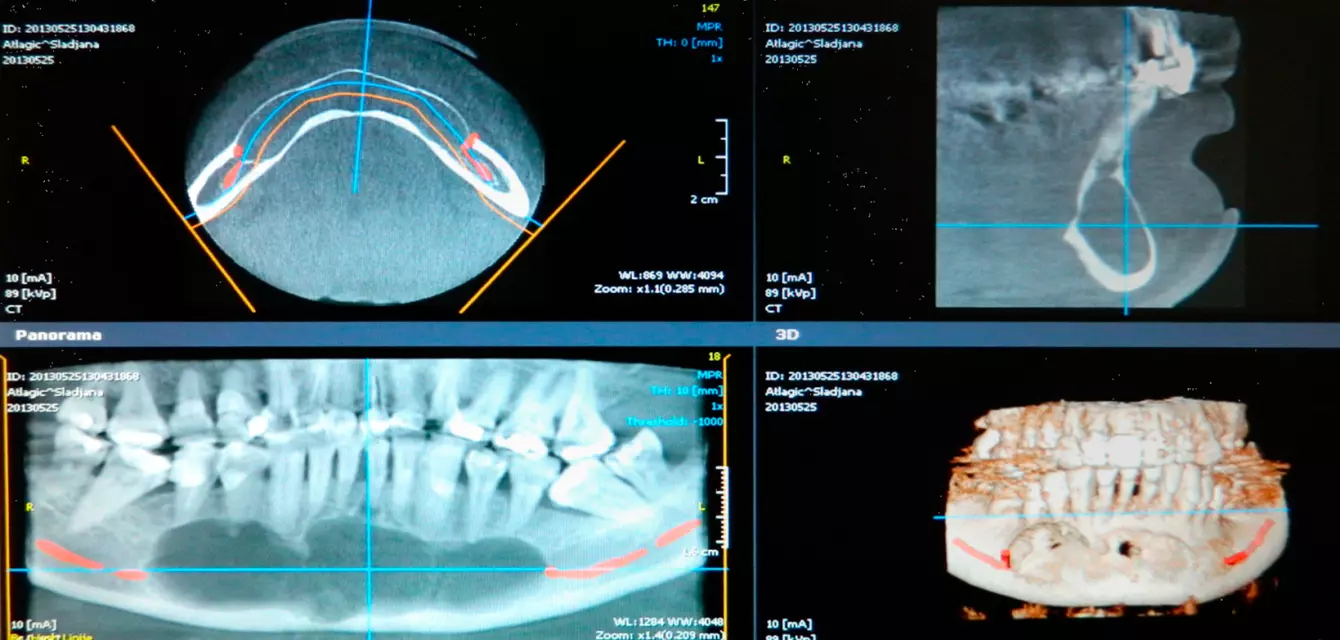

Ukoliko su vam potrebni zubni implanti, Stomatološka poliklinika dr Džolev je specijalizovana kada je pružanje usluga iz ove oblasti u pitanju.

Kada su u pitanju zubni implanti, naši zaposleni su tu da vam u svakom momentu daju odgovor, savet ili pomoć. Odlikuje nas pouzdanost, profesionalnost, stručnost i brzina.